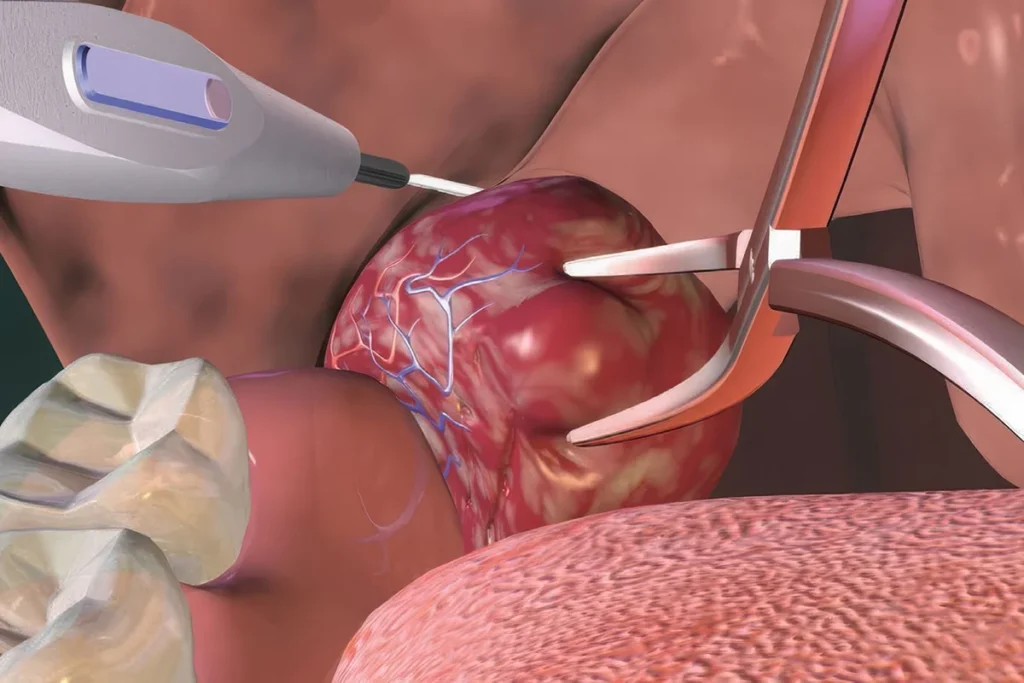

Geniz Eti Koblasyon Ameliyatı Nedir? Belirtileri, Tedavisi…